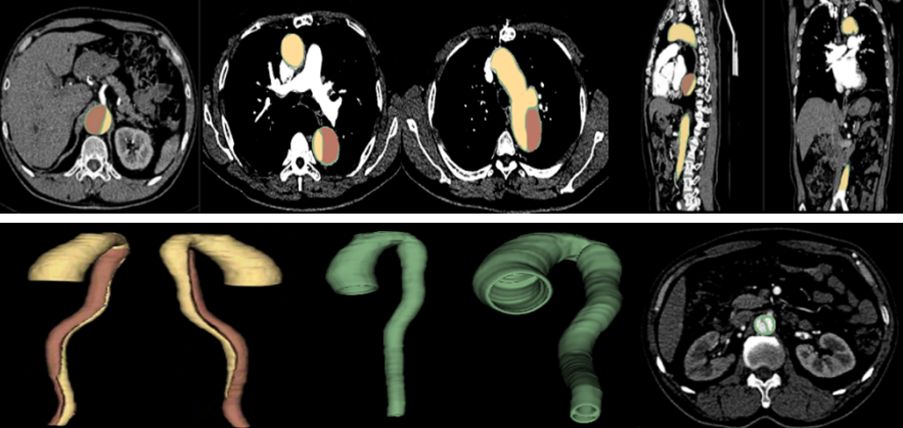

汇医慧影公司联合北京301解放军医院总院,借助NVIDIA GPU,将深度学习技术应用至B型主动脉夹层分割及破口检测的多任务学习。汇医慧影利用大量带有主动脉及夹层手动标注的三维CTA 图像,提出了基于深度卷积神经网络的夹层分割方案。在此基础上可确定破口位置,并计算夹层形态参数,为医生提供临床决策支持。

基于手动分割的金标准图像,分别得到主动脉、真腔和假腔的二值化标注。主动脉壁和内膜片可以通过主动脉标注减去真假腔标注得到。

其多任务深度学习网络如下图所示。卷积层和反卷积层的参数被三个任务共享:主动脉分割、真腔分割、假腔分割。每个任务均属于二值分割。

三个分割任务的损失函数在训练过程中同时得到优化。模型采用原始的3D CTA图像作为输入,输出为主动脉、真腔和假腔的二值化掩膜。